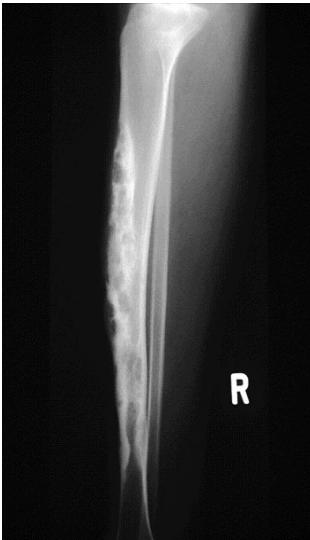

Other Diaphyseal Lesions

Could be malignant, even though no periosteal reaction, may be due old fracture

Pathological fracture, after metastasis

Important Diagnostic Note

Always remember infection as differential diagnosis